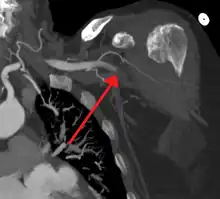

![]() | |

Acute embolism to the right femoral artery resulting in ischemia | |